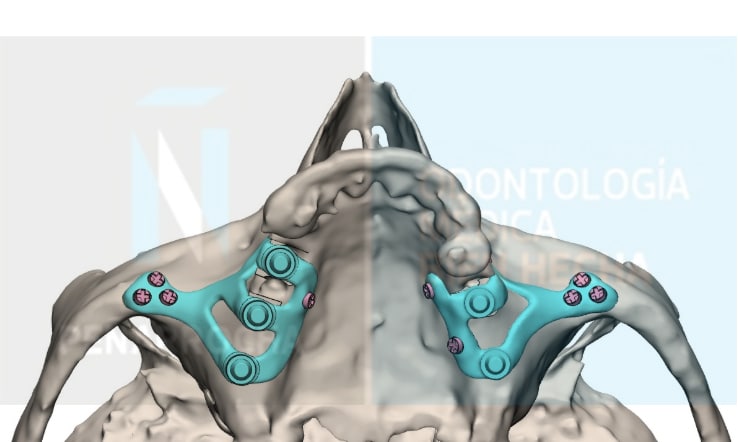

Aunque se colocan desde hace más de 50 años, la técnica ha evolucionado gracias a la odontología digital. Actualmente, se pueden diseñar y fabricar con mayor precisión mediante escáneres 3D o software CAD/CAM. Estas tecnologías innovadoras en el proceso de producción junto con la utilización de nuevos materiales y procedimientos de colocación, permiten obtener una adaptación perfecta a la anatomía de cada paciente y resultados mucho más predecibles.

Se diseñan y fabrican a medida mediante tecnología digital (CBCT, CAD/CAM, sinterización láser), lo que permite un ajuste preciso a la superficie del hueso maxilar y a la anatomía del paciente.

3. Diseño personalizado del implante

Con la información obtenida del estudio, el equipo diseña de forma digital los implantes a medida y se planifica su posición sobre la pantalla del ordenador. A partir de este diseño, se fabrican unas férulas quirúrgicas que guiarán la colocación del implante subperióstico durante la cirugía, asegurando que la estructura se adapte perfectamente al hueso del paciente.

4. Colocación de los implantes

La intervención se lleva a cabo bajo anestesia local o sedación consciente. El cirujano realiza una incisión lingualizada o palatinizada para conseguir la mayor cantidad posible de encía queratinizada por vestibular y coloca la estructura sobre el hueso, debajo del periostio. En muchos casos es posible realizar una carga inmediata, colocando una prótesis fija provisional atornillada el mismo día de la cirugía.